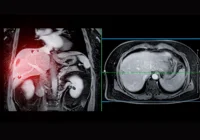

The nonspecific nature of PDAC symptoms often delays clinical diagnosis, underscoring the need for radiologists to detect early imaging markers. MRI outperforms CT in identifying small or isoattenuating pancreatic lesions, which are frequently missed on standard imaging protocols. Key early signs include main pancreatic duct (MPD) dilation, contour deformities, focal atrophy and the “double duct” sign—simultaneous dilation of the bile and pancreatic ducts. Retrospective studies have revealed that such indicators often appear on imaging months or even a year before clinical diagnosis. The presence of MPD calibre changes, focal pancreatic atrophy or pancreatic fat infiltration should prompt further evaluation through advanced imaging or endoscopic ultrasound.

Cystic lesions also warrant attention. Intraductal papillary mucinous neoplasms (IPMNs), especially those involving the main duct or both main and branch ducts, carry a substantial risk of malignant transformation. Branch duct IPMNs (BD-IPMNs), although less aggressive, still present a tangible long-term risk. Features such as cyst size over 30–40 mm, mural nodules and MPD dilation over 10 mm signal higher malignancy potential. Mucinous cystic neoplasms (MCNs), predominantly found in women, typically present as solitary cysts in the pancreatic body or tail and also harbour malignant potential. Imaging characteristics, including cyst wall thickening and the presence of enhancing nodules or septations, help differentiate MCNs from benign entities.

However, full MRI protocols are time-consuming, often exceeding 30 minutes, which challenges their routine application. To mitigate this, abbreviated MRI protocols have been proposed, reducing scan times to 15–20 minutes by excluding certain sequences. These streamlined approaches are especially effective in follow-ups for cystic lesions like IPMNs. Emerging technologies such as artificial intelligence and radiomics may further enhance early detection by enabling opportunistic screening on routine imaging performed for unrelated indications.